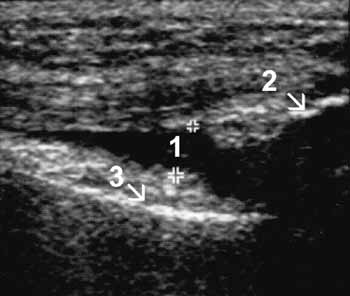

Рис. 2. I стадия остеоартроза. Умеренное увеличение b. suprapatellaris

(1+) с наличием избытка относительно однородной жидкости, 2 — надколенник, 3

— бедренная кость.